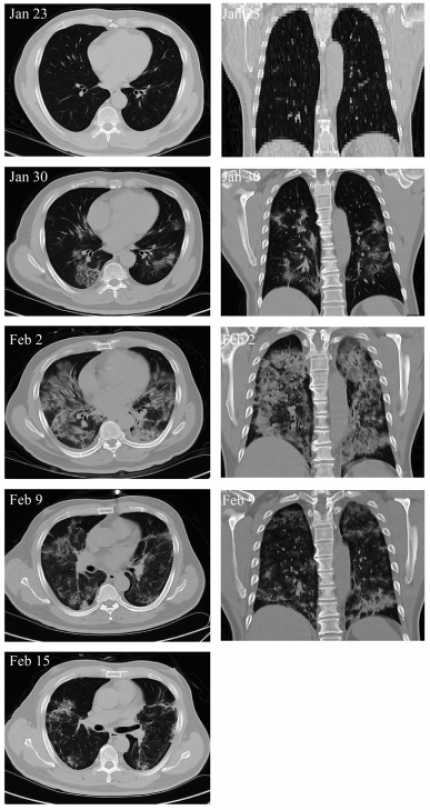

В Пекинском университете для лечения 65-летней китаянки, использовали мезенхимальные стволовые клетки из пуповинного канатика. На момент начала клеточной терапии пациентка была в критическом состоянии, несмотря на то, что стандартное лечение от коронавируса ей проводили уже на протяжении недели. Перед первой инъекцией у женщины в крови упало количество эритроцитов, а лейкоциты повысились до тревожных значений, налицо были признаки дыхательной недостаточности, поражения печени, анемии. Состояние пациентки усугублялось еще и гипертонией, диабетом 2 типа и желудочными кровотечениями. За курс лечения пуповинными стволовыми клетками женщине ввели три инъекции с интервалом в 3 дня - спустя несколько дней после этого ее состоянии значительно улучшилось, в легких стали исчезать очаги воспаления, что подтвердила компьютерная томография. По итогам клеточной терапии все жизненно-важные показатели состояния здоровья женщины вернулись к норме, а тест на наличие COVID-19 показал отрицательный результат.